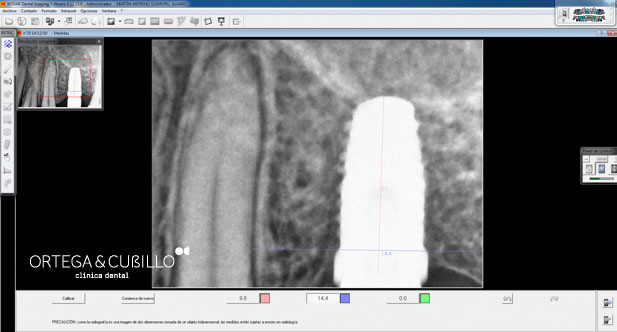

Realizamos ortopantomografías y telerradiografías que son pruebas radiológicas de gran importancia en el tratamiento de ortodoncia e implantología. Asimismo se pueden realizar pequeñas tomografías, radiología de la articulación temporomandibular , senos maxilares y muñeca en este caso para determinar el estado de maduración ósea durante el crecimiento.

También disponemos de aparatos de radiológia dental mediante radiovisiografía Una herramienta que también facilita el diagnóstico y mejora la calidad de nuestros tratamientos.